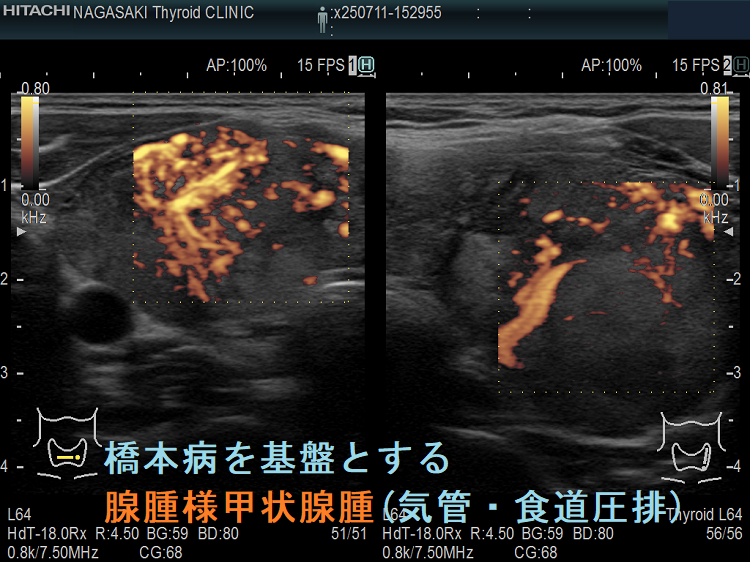

ケース④ 橋本病を基盤とする腺腫様甲状腺腫(気管・食道圧排)

橋本病を基盤とする腺腫様甲状腺腫(気管・食道圧排) 矢状断;等エコーなので甲状腺悪性リンパ腫が隠れているようには見えないが、潜在性甲状腺癌(甲状腺ラテント癌)が存在する可能性は否定できない。かなり気道圧迫している。